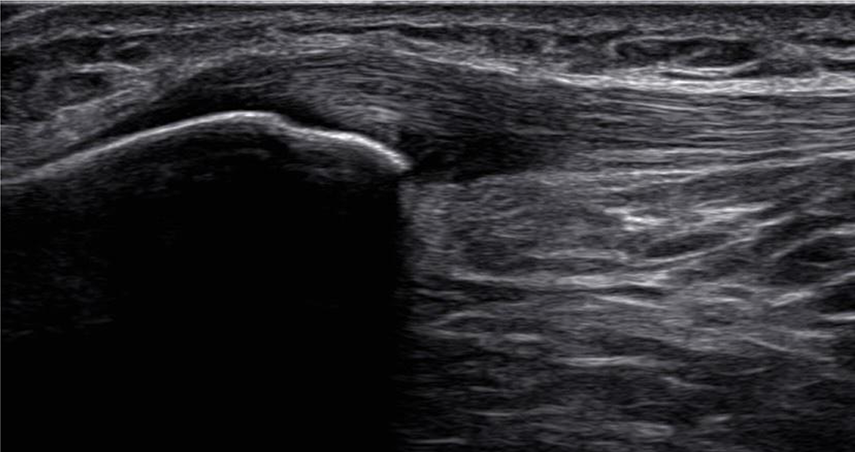

膝蓋腱の超音波画像

aは正常の膝蓋腱長軸像であり、腱実質はfibrillar patternを呈している。bはジャンパー膝例であり、膝蓋腱近位深層でfibrillar patternの消失が観察される。